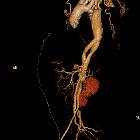

Aortendissektion bei Aortenisthmusstenose

CT, especially with arterial contrast enhancement (CTA) is the investigation of choice, able not only to diagnose and classify the dissection but also to evaluate for distal complications. It has reported sensitivity and specificity of nearly 100% .

Contrast-enhanced CT (preferably CTA) gives excellent detail. Findings include :

- intimal flap

- double-lumen

- dilatation of the aorta

An essential part of the assessment of aortic dissection is identifying the true lumen, as the placement of an endoluminal stent-graft in the false lumen can have dire consequences. Distinguishing between the two is often straightforward, but in some instances, no clear continuation of one lumen with normal artery can be identified. In such instances, a number of features are helpful :

- true lumen

- often compressed by the false lumen and the smaller of the two

- outer wall calcifications (helpful in acute dissections)

- origin of the coeliac trunk, SMA and right renal artery usually arise from the true lumen

- false lumen

- often larger lumen size due to higher false luminal pressures

- at risk for rupture due to reduced elastic recoil and dilation

- beak sign

- cobweb sign (as slender linear areas of low attenuation specific to the false lumen due to residual ribbons of media that have incompletely sheared away during the dissection process)

- often of lower contrast density due to delayed opacification

- maybe thrombosed and seen as mural low density only (more common in chronic dissections)

- the left renal artery usually arises from the false lumen

- surrounds true lumen in Stanford type A